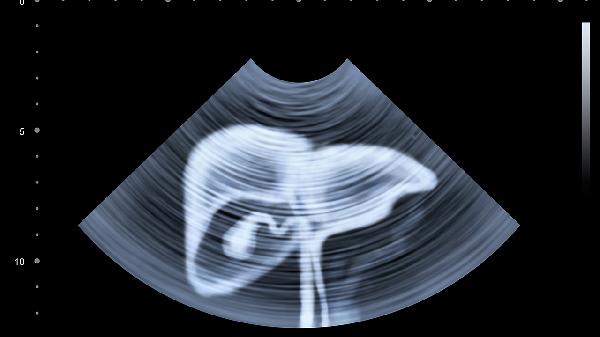

1、定期体检不能少

肝功能检查、肝脏B超、甲胎蛋白检测,这三项检查每年至少做一次。